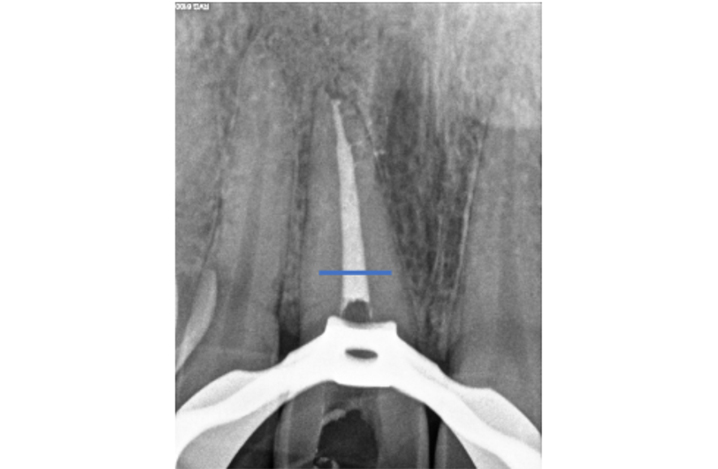

Figure 1: Pulp canal obliteration (PCO). The patient had trauma to UL1 15 years ago and developed a yellow discolouration over time. She was keen to improve the appearance of the tooth. The UL1 was asymptomatic and did not respond to sensibility testing.

Radiographically, UL1 had a normal PDL width and an intact lamina dura could be seen around the tooth. A diagnosis of pulp canal obliteration was reached for UL1. There was no endodontic infection and the patient was advised to have external tooth whitening; this will take longer and a veneer might be necessary if a satisfactory result can’t be achieved with external whitening alone. Figure 1a: Preoperative photograph. Figure 1b: Preoperative radiograph.